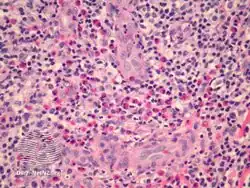

Epithelioid haemangioma in skin | |

Epithelioid haemangioma is a non-cancerous tumor typically found in skin and soft tissue of usually the head and neck region, where it presents with reddish-pink itchy painful bumps.[1] It can occur in bone as a type of vascular tumor of bone, where it can give rise to pain and swelling.[2]

It is made up of well-formed blood vessels lined by lymphocytes and eosinophils (types of white blood cells).[1]